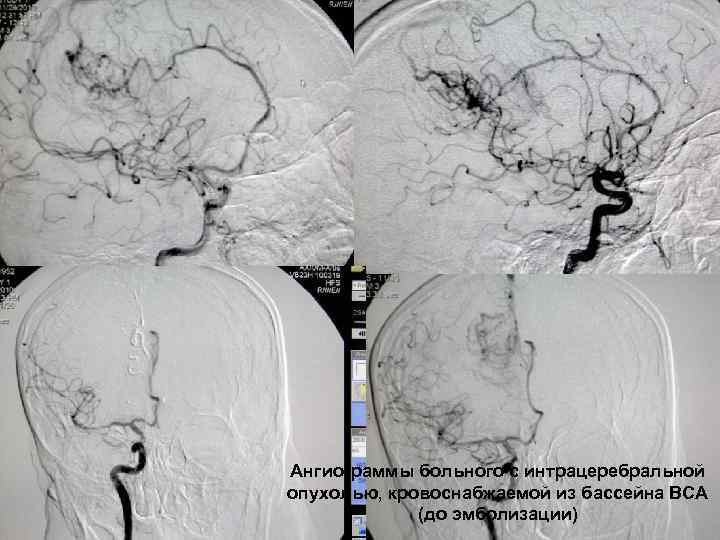

Ангиограммы больного с интрацеребральной опухолью, кровоснабжаемой из бассейна ВСА 60 (до эмболизации)